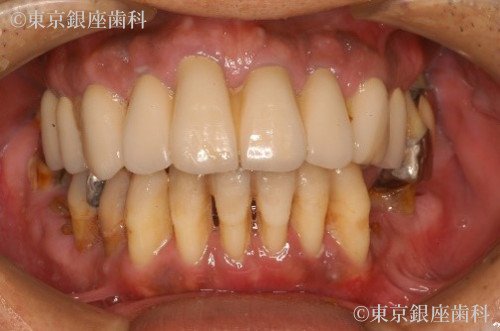

After

抜歯即時埋入でインプラント治療を行い、その日のうちに仮歯を入れて短期間での大幅な審美、機能の回復をした。

また上顎骨が薄くインプラント埋入の難しい部位には人口骨を足しインプラント埋入を可能にした。